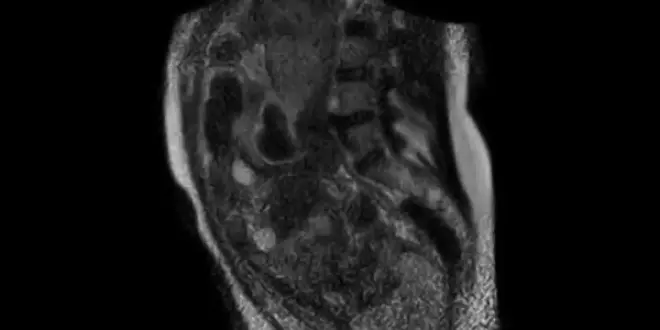

La jeune mère a accouché dans un appareil d'IRM spécial, puisqu'il s'agit d'un appareil ouvert développé à l'origine pour les patients claustrophobes. Grâce à ce dispositif et à une caméra sans film compatible avec l'IRM, les chercheurs ont pu suivre, dans une résolution d'image de qualité suffisante, les battements du cœur du fœtus, également la position des squelettes de l'enfant à naître et de la mère.

"Ils ont pu avoir accès en temps réel à une description anatomique au niveau du pelvis et du périnée, ça permet de mieux comprendre ce qu'il y a de traumatisant pour l'anatomie de la mère et comment le foetus s'engage", précise le Dr Guillaume Gorincour, radiologue au service d'imagerie pédiatrique et prénatale à l'hôpital de la Timone à Marseille, contacté par la rédaction d'Allodocteurs.fr.